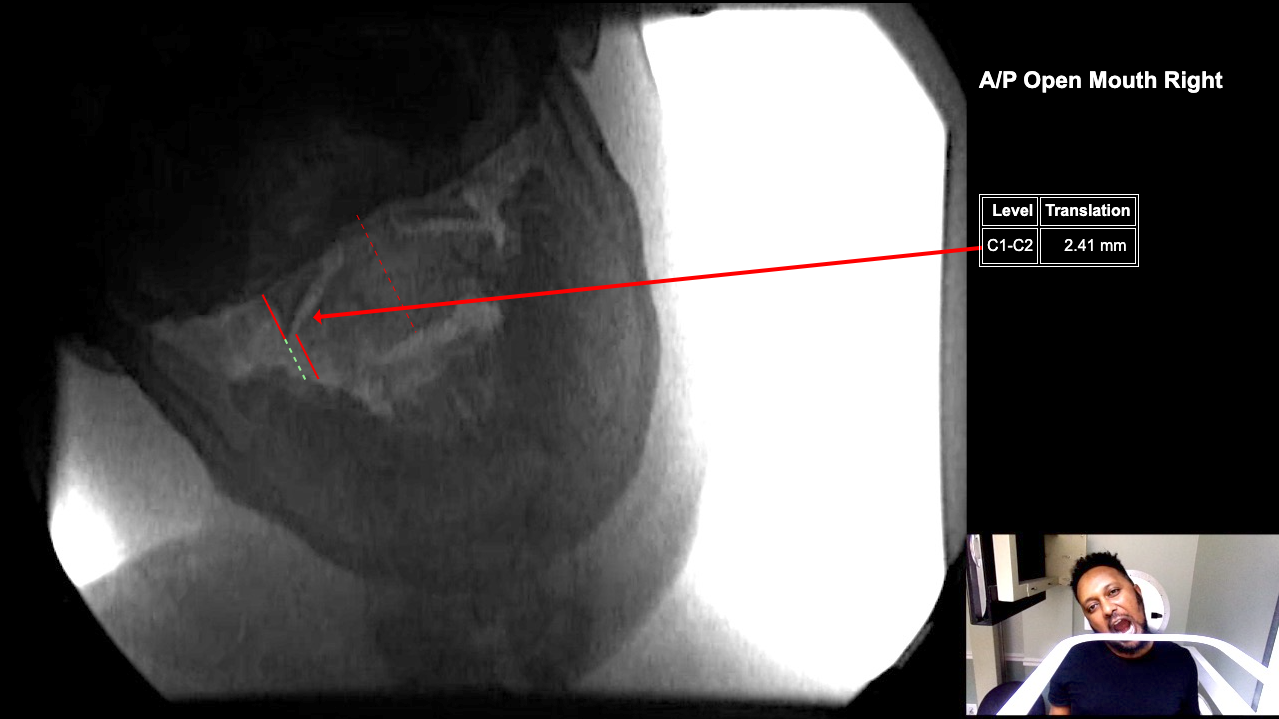

Image 2